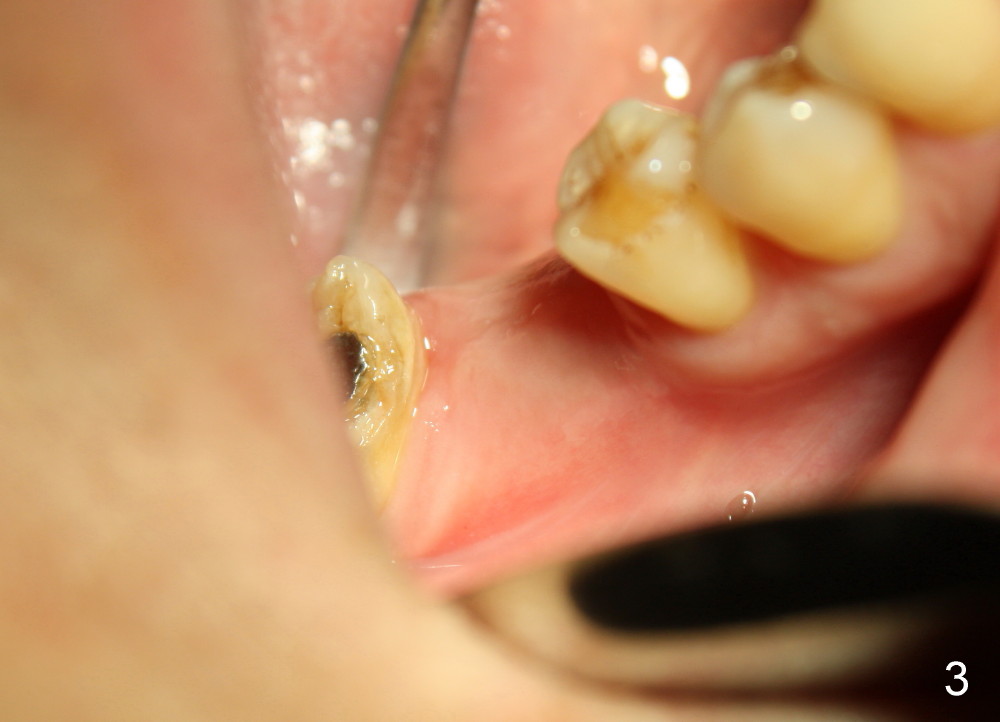

Fig.1 and 2 show a 5.3x12 mm bone level implant immediately and 6.5 months post placement, respectively. The gingiva looks normal at the site of #30 6.5 months postop (Fig.3). A small incision is made for uncover and a large healing abutment (9.2 mm) is placed (Fig.4 (buccal view), 5 (lingual)). It appears that an interdental papilla forms instantaneously (Fig.4 *). The wound is covered by periodontal dressing. To reduce the chance of post-implant infection, several things should be done. First. the extraction socket should be thoroughly debrided, copiously irrigated and soaked with an antibiotic. Second, any gaps remaining after implant placement should be filled with bone graft, which could be mixed with an antibiotic. Third, the wound should be closed as tight as possible. Either the implant is buried (bone level) or a short abutment over a tissue-level implant or healing abutment over a bone level implant is placed so that periodontal dressing can be applied around the wound. Fourth, an antibiotic is taken pre- and post-op. There is no bone loss around the implant 21 months post cementation (Fig.6) or 4 years 9 months post cementation (Fig.7). Return to Professionals Implant Failure Xin Wei, DDS, PhD, MS 1st edition 07/26/2014, last revision 06/13/2019